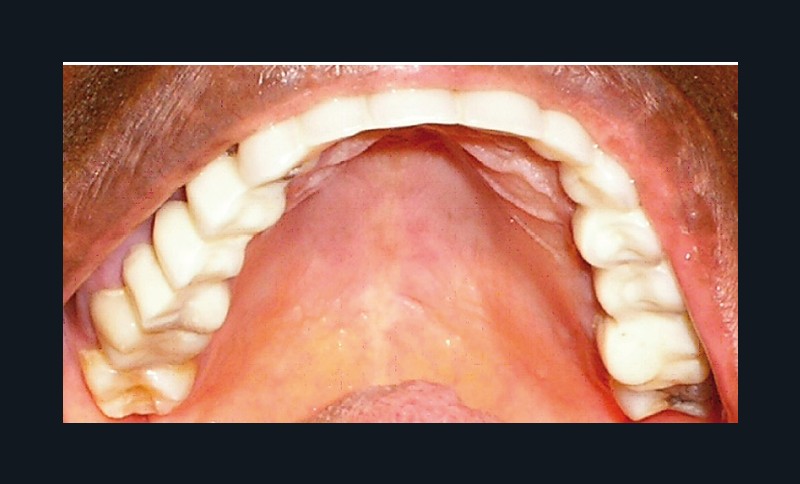

La patiente a été porteuse d’un bridge céramo-métallique de onze éléments au maxillaire pendant huit mois (fig. 1, 2), puis d’un bridge transitoire au maxillaire (fig. 3). Elle signale quelques rares épisodes de saignement probablement dus à l’irritation par la prothèse. Cette dernière se descelle couramment, créant ainsi un préjudice fonctionnel, esthétique et psychologique.

La prothèse transitoire issue du wax-up est posée (fig. 12a-d). Elle constitue une véritable proposition thérapeutique au plan occluso-fonctionnel, parodontal, esthétique et psychologique.

Contrôle et maintenance : la patiente a été revue une semaine plus tard, puis à un mois, et ensuite six mois après le scellement pour les contrôles(fig. 20). Elle est satisfaite, aussi bien sur le plan esthétique que fonctionnel, en adéquation avec ses attentes.